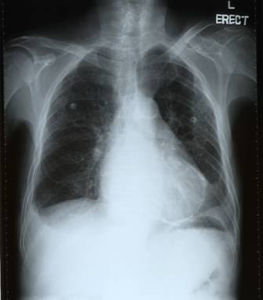

X射線下心包炎急性心包炎可為漿液性,纖維素性,出血性或化膿性。心外膜下心肌的表層可能受累。細胞反應的量和性質取決於病因.。

X線檢查

心包炎積液量超過毫升時心影向兩側增大心隔角變成銳角超過毫升時心影呈燒瓶狀並隨體位而異心臟搏動減弱或消失。

胸部X光片和心電圖也能作出診斷,最簡單而正確的診斷方法是心臟B超,特別經治療後,能了解積液減少情況。